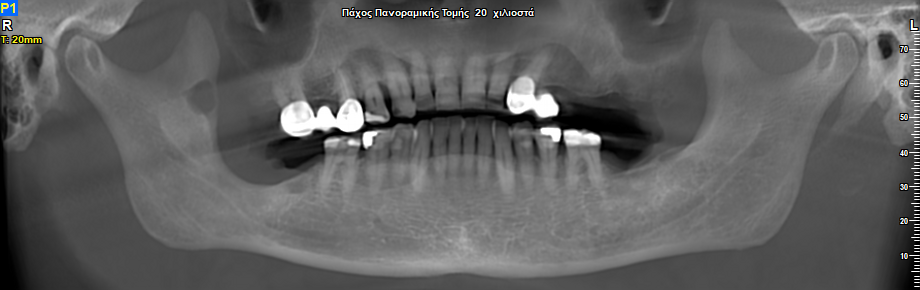

Άνδρας ασθενής 77 ετών εμφάνισε προ 4 ετών ενδοστοματικό ογκίδιο για την ακτινολογική διερεύνηση του οποίου συστήθηκε η πραγματοποίηση πανοραμικής ακτινογραφίας. Στην πανοραμική ακτινογραφία παρατηρήθηκε η παρουσία ευμεγέθους ακτινοδιαυγαστικής αλλοίωσης η οποία απεικονίζεται στην περιοχή της αναφερόμενης ενδοστοματικής βλάβης.

Πανοραμική Ακτινογραφία 12/2020